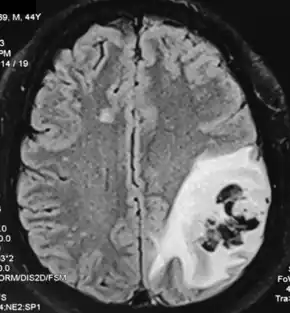

Stroke after intravenous immunoglobulin (in a case of Miller Fisher syndrome)

Although immunoglobulin is frequently used for long periods of time and is generally considered safe, immunoglobulin therapy can have severe adverse effects, both localized and systemic. Subcutaneous administration of immunoglobulin is associated with a lower risk of both systemic and localized risk when compared to intravenous administration (hyaluronidase-assisted subcutaneous administration is associated with a greater frequency of adverse effects than traditional subcutaneous administration but still a lower frequency of adverse effects when compared to intravenous administration). Patients who are receiving immunoglobulin and experience adverse events are sometimes recommended to take acetaminophen and diphenhydramine before their infusions to reduce the rate of adverse effects. Additional premedication may be required in some instances (especially when first getting accustomed to a new dosage), prednisone or another oral steroid.